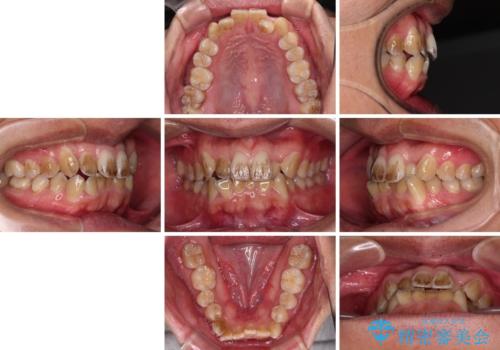

- 前歯のデコボコを気にして来院された患者様です。

極力費用を抑えた上で、自己管理の煩わしの少ない装置を希望とのことで、メタルブラケットによるワイヤー矯正を選択されました。

舌の突出癖があり、デコボコが解消される際に出っ歯傾向になる恐れがあるため、舌のトレーニングを行っていただきながら、矯正治療を進めていくこととしました。